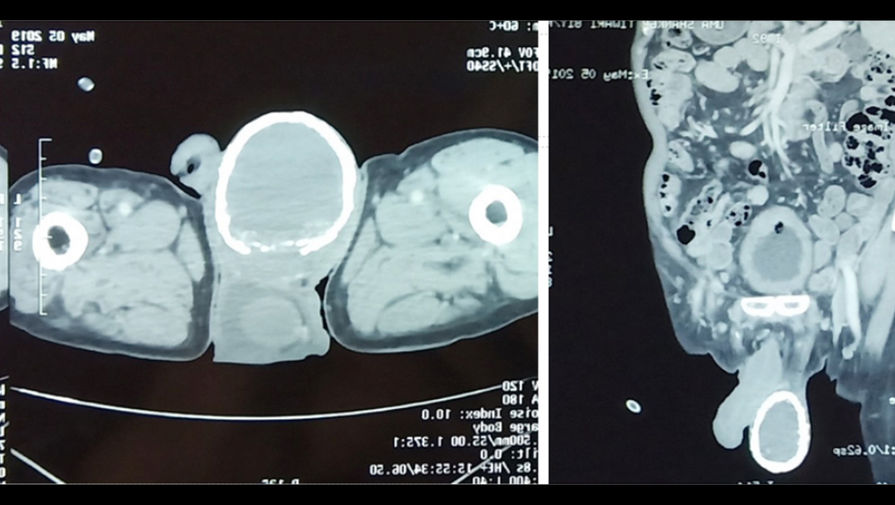

80-летний пациент, обнаружив у себя в моче кровь, поспешил обратиться к врачам. На осмотре те обнаружили еще одну проблему — правое яичко мужчины увеличилось в несколько раз и было твердым как камень. Компьютерная томография показала: у мужчины водянка яичка (гидроцеле). При этом заболевании между оболочками яичек скапливается серозная жидкость. Гидроцеле может быть как врожденным, так и приобретенным, во втором случае оно возникает в результате травм, операций на половых органах, воспалительных заболеваний яичка. Как правило, приобретенная водянка проходит по мере лечения основного заболевания. Возможно и оперативное лечение.

Однако при водянке мошонка остается мягкой, а у пациента она была твердой.

Как оказалось, причина этого — толстый слой кальция, сформировавший внутри своеобразную «скорлупу».

<1>Кальцификация, отложения солей кальция — само по себе нередкое явление. Ее причиной могут стать травмы, операции, почечная недостаточность. В данном случае ее спровоцировала водянка, считают врачи. С таким проявлением кальцификации они столкнулись впервые — впервые подобное отложение кальция было описано в 1935 году и с тех пор известно лишь о нескольких подобных случаях.